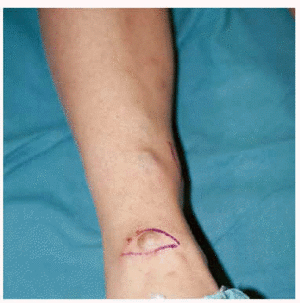

Algunas de las tumoraciones blandas, las que producían dolor, se extirparon y se realizó estudio histopatológico que demostró la presencia de espacios anfractuosos tapizados por endotelio y a menudo ocupados por trombos y hemorragias (fig. 3). En el abundante tejido interpuesto, además de fibrosis hay haces de células fusiformes con vacuolización citoplasmática (fig. 4) que caracteriza la entidad conocida como hemangioendotelioma, o actualmente hemangioma de células fusiformes.